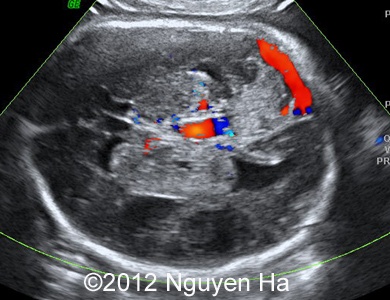

A 30-year-old woman (G1P0), with unremarkable family history, presented to our unit at 36 weeks of her pregnancy. She did not undergo any previous screening tests. Our examination (and repeated scan after four days) revealed following findings:

Figures 1-7: 36 wekks of pregnancy.

A 30-year-old woman (G1P0), with unremarkable family history, presented to our unit at 36 weeks of her pregnancy. She did not undergo any previous screening tests. Our examination revealed unilateral hypoechoic inhomogeneous mass within cerebral parenchyma. Our initial diagnosis was teratoma, but repeated exam after four days showed structural changes and different echogenicity of the mass and so our final diagnosis was cerebral hemorrhage. The findings were confirmed by MRI scan.

Figure 1-7: 36 wekks of pregnancy.